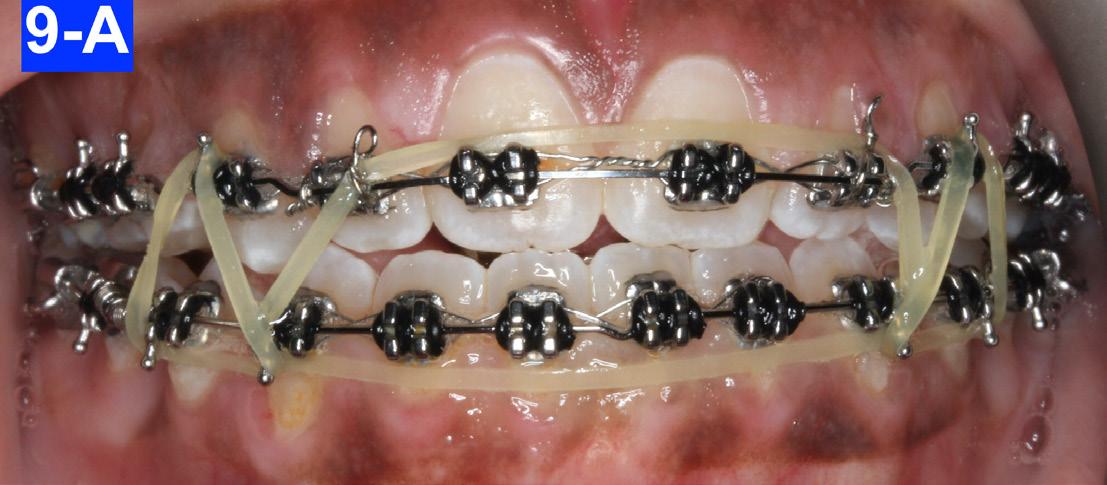

After eight months of treatment, the maxillary habit breaker was removed. We added box elastics (5/16” x 6.5 oz) that were stretched around the mandibular cuspids and maxillary laterals, to accelerate the closing of the anterior open bite. The patient was already very happy with the progress and the amelioration of her posed smile (Figure 9-A, B, C, D).

Fig. 9-A: Box elastic. Frontal view